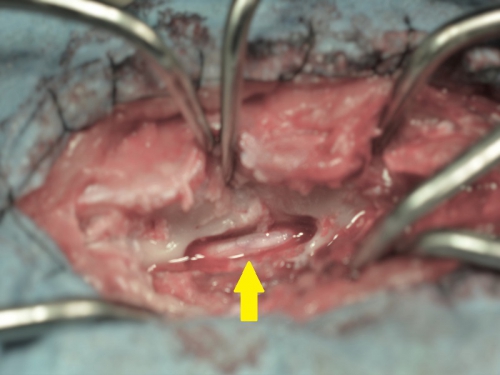

手術方法にはいくつかの方法があり、最も多く行われるのが、背中側から圧迫物質を除去して減圧する片側椎弓切除術や椎弓切除術、頸部の椎間板ヘルニアに対しては腹側(喉側)から行うベントラルスロット(腹側造窓術)が多用されます。いずれの方法も下の写真のように椎骨の一部に「窓」を形成して脊髄神経への圧迫を減圧して、飛び出した椎間板物質(黄緑矢印)を除去するということを基本とします。

下の写真は片側椎弓切除術(ヘミラミネクトミー)を実施した後の術中写真です。黄色矢印が、椎弓(背骨の一部)を切除して減圧された脊髄です。内部に見られる白い棒状のものが脊髄神経です。この写真では脊髄を圧迫していた物質は既に除去されております。